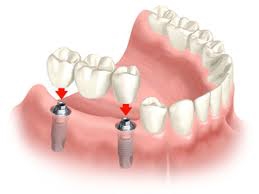

种植牙是一种缺牙的修复方法,也称为人工种植牙,它利用高度相容性的材料制成类似于牙根形状的植体,再将其植入缺牙区的骨质,通过制作安装植体上部的假牙冠而最终达到恢复缺失牙的外形和功能目的。种植牙已发展成为一项成熟、可靠、成功率高的新技术,并且随着人们口腔卫生保健意识的增强,大众对牙齿的要求越来越高,对种植牙的接受度不断提高,该技术在国内外已经逐渐成为病人和口腔医师乐于采用的一种常规修复缺牙方式。

与传统固定活动义齿修复相比,种植牙因其不损伤周围牙、固位稳固、美观舒适等优点,逐渐成为很多牙齿缺失患者的选择,有人类“第三副牙齿”的美誉。人工种植牙具有六大突出优点:

通过外科手术将人工牙根植入牙床内,经过一段愈合期后,人工牙根与牙槽骨发生骨结合,再在人工牙根上镶装义齿,修复缺失的牙齿。